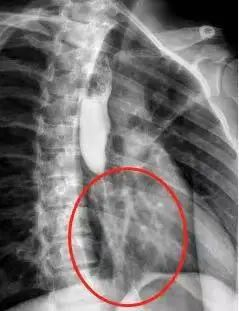

再去医院复诊时,影像结果显示,他的食管中下端居然细成了一根“线”:食管内壁结了厚厚的痂,几乎塞满整个食管,导致食物无法顺利通过,中间最宽的地方只有3毫米左右的空间。

▲小蔡的中下端食管细成一条线原来,小蔡误服的空调清洗剂是一种强碱。